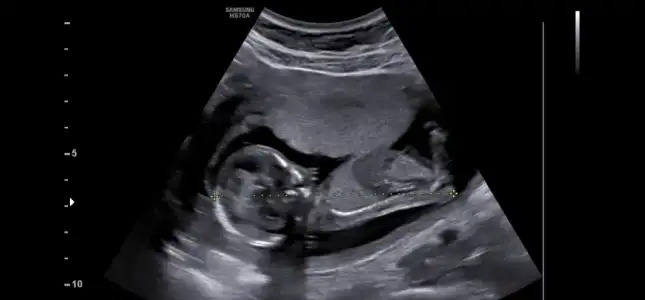

Cinsiyet tahmini

Ben boş görüyorum ama gören herkes erkek diyor bana belittilerim falan da hep erkekmiş

Net erkek bence